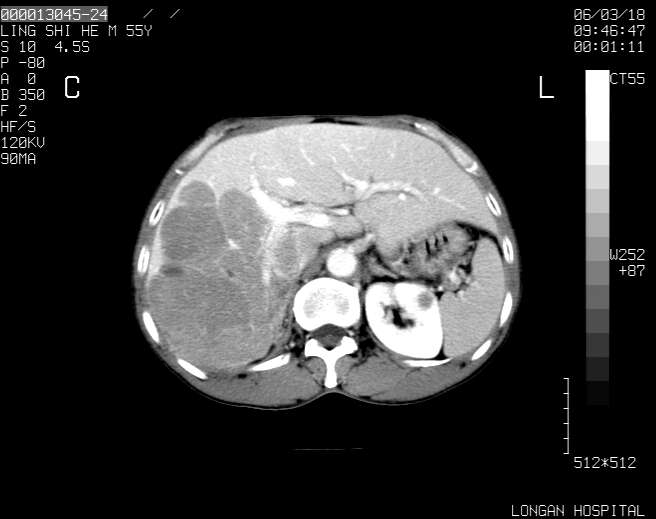

以下是引用guzhongliangddd在2006-3-21 22:13:00的发言:[br]病灶主要位于肝右叶的后份,内见异常血管,门脉主干及右支受侵{提示有癌栓形成},门腔间隙内见增大淋巴结。肝左叶内未见异常。

以下是引用zhuxinli在2006-3-22 1:23:00的发言:[br][br] 病灶主要位于肝右叶的后份,内见异常血管 .门脉右支截断,右叶前段早期强化(考虑动静脉漏),腹膜后肿大淋巴结,病灶逐渐强化,考虑为胆管细胞癌[br]